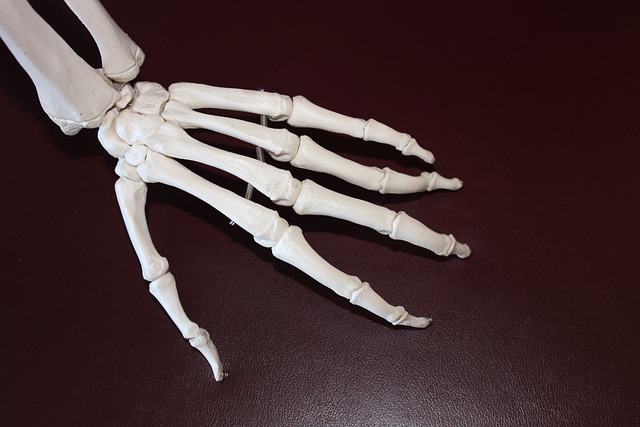

콘드로이친은 자연적으로 우리 몸 안의 연골 구조에 존재하는 중요한 물질로, 주로 동물의 연골에서 추출하여 보충제 형태로 널리 사용됩니다.

이 물질은 연골의 탄력성을 유지하고, 외부 충격을 흡수하는 중요한 역할을 하여, 관절의 건강을 지키는 데 기여합니다. 특히 나이가 들면서 연골이 자연스럽게 마모되거나 손상될 수 있는데, 이때 콘드로이친을 보충하는 것은 손상된 연골의 회복을 지원하고, 이로 인한 관절 통증을 완화시키며, 장기적으로 관절의 기능을 향상하는 데 도움을 줄 수 있습니다.

더불어, 콘드로이친은 연골 내에 수분을 보유하는 능력을 높여, 연골이 건강하고 탄력적인 상태를 유지할 수 있도록 지원합니다. 이러한 특성으로 인해, 콘드로이친은 연령이 증가함에 따라 겪을 수 있는 관절 문제의 예방과 관리에 매우 중요한 역할을 하며, 많은 사람들에게 필수적인 보충제로 인식되고 있습니다.